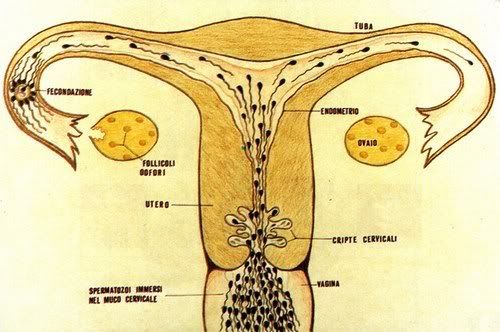

La gravidanza procede bene ed ormai siamo veramente agli sgoccioli. Girovagando per internet guardate cos'ho trovato....incredibile....è veramente il MIRACOLO DELLA VITA

La gravidanza procede bene ed ormai siamo veramente agli sgoccioli. Girovagando per internet guardate cos'ho trovato....incredibile....è veramente il MIRACOLO DELLA VITA